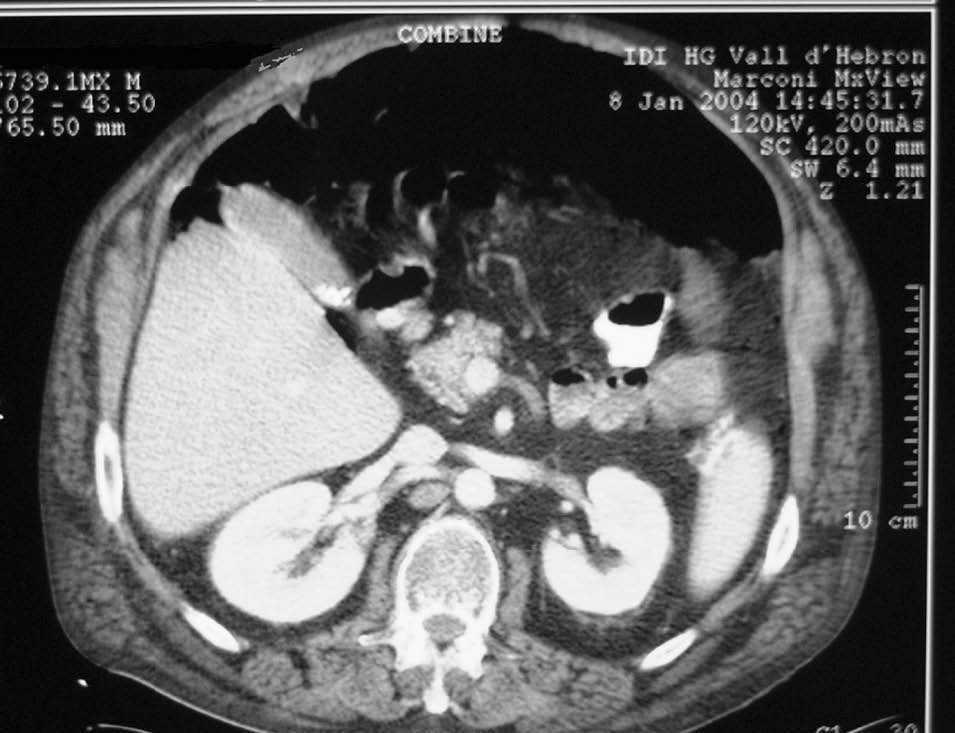

Ingresó en el servicio de neumología por un cuadro de sobreinfección respiratoria que evolucionó con una mala respuesta al tratamiento, con desarrollo de una insuficiencia respiratoria grave que precisó un ingreso en la unidad de cuidados intensivos (UCI) con intubación orotraqueal y ventilación mecánica. La evolución posterior fue satisfactoria y el paciente fue extubado y dado de alta de UCI a la planta de neumología al sexto día. A su llegada a planta el paciente presentó un empeoramiento de su estado general acompañado de distensión y dolor abdominal difuso, sin signos de irritación peritoneal y la aparición nuevamente de cuadro de insuficiencia respiratoria. Se realizó una tomografía computarizada abdominal de urgencia, donde se evidenció la presencia de un neumoperitoneo masivo (fig. 1). Se decidió realizar una intervención quirúrgica urgente, practicándose una laparotomía exploradora sin que se observara una perforación de víscera hueca ni ninguna otra causa intraabdominal de neumoperitoneo. El paciente siguió un curso posterior satisfactorio, tanto de la laparotomía como del cuadro respiratorio, y fue dado de alta hospitalaria al 10 día postoperatorio.

Fig. 1. Imagen de tomografía computarizada con neumoperitoneo masivo. Obsérvese la gran distensión abdominal secundaria a la presencia de aire en el interior.